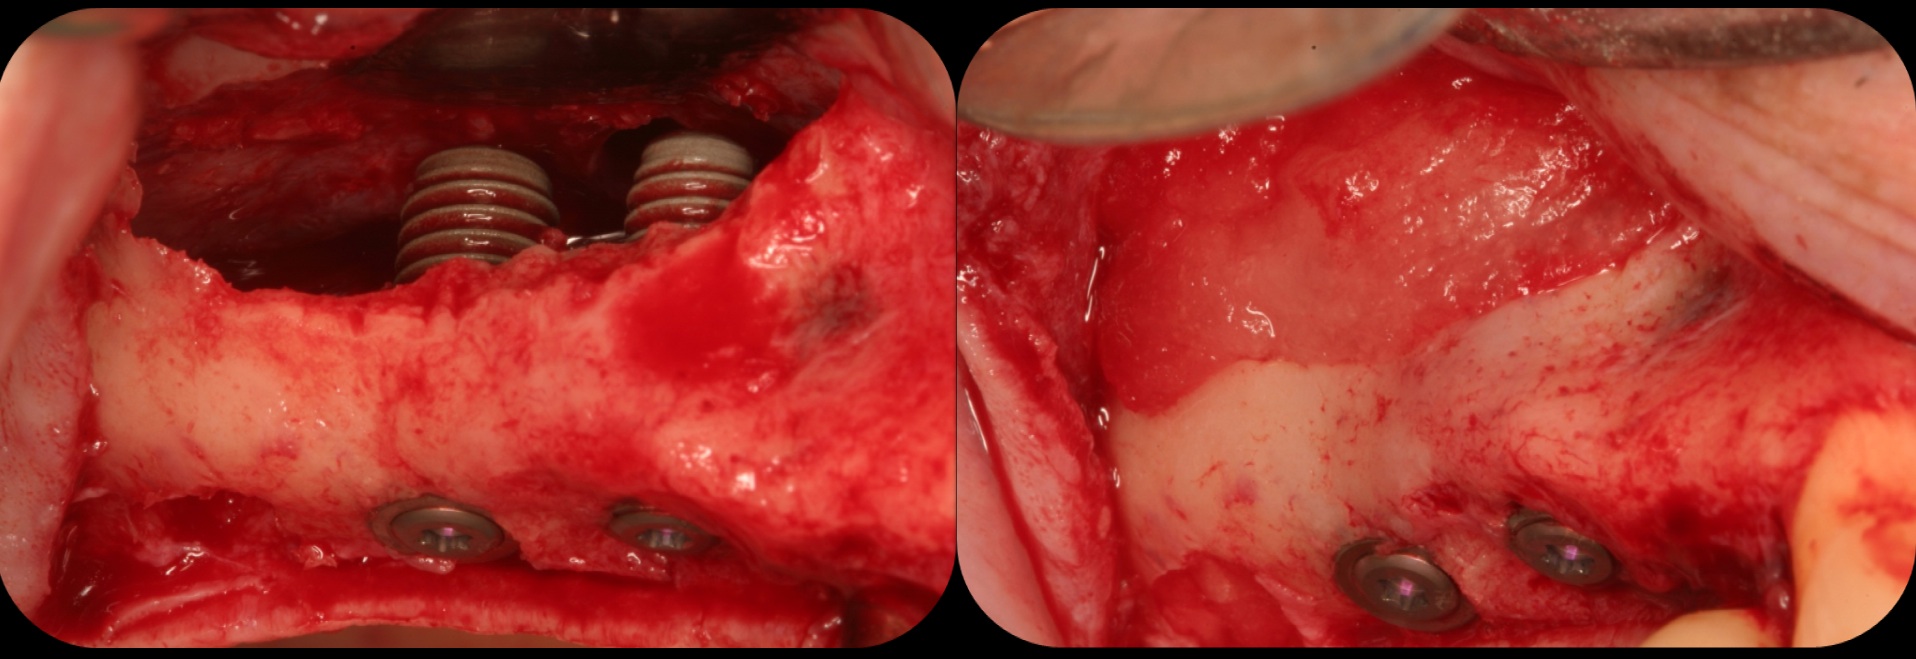

Facial bone loss and a mesial vertical defect.

Fig. 3

Application of enamel matrix derivative.

Fig. 4

Demineralized freeze-dried bone allograft.

Fig. 5

Evidence of clinical attachment gain.

Fig. 6

The 9-year postoperative radiograph.

Fig. 7

Then, too, are opportunities to prepare the site for regeneration by coupling therapies, applying an enamel matrix derivative, along with traditional bone grafts of demineralized freeze-dried bone allograft; potentially, gains in attachment with minimal probing depth and retained papilla may avoid the need for an implant (Figure 2 through Figure 7).